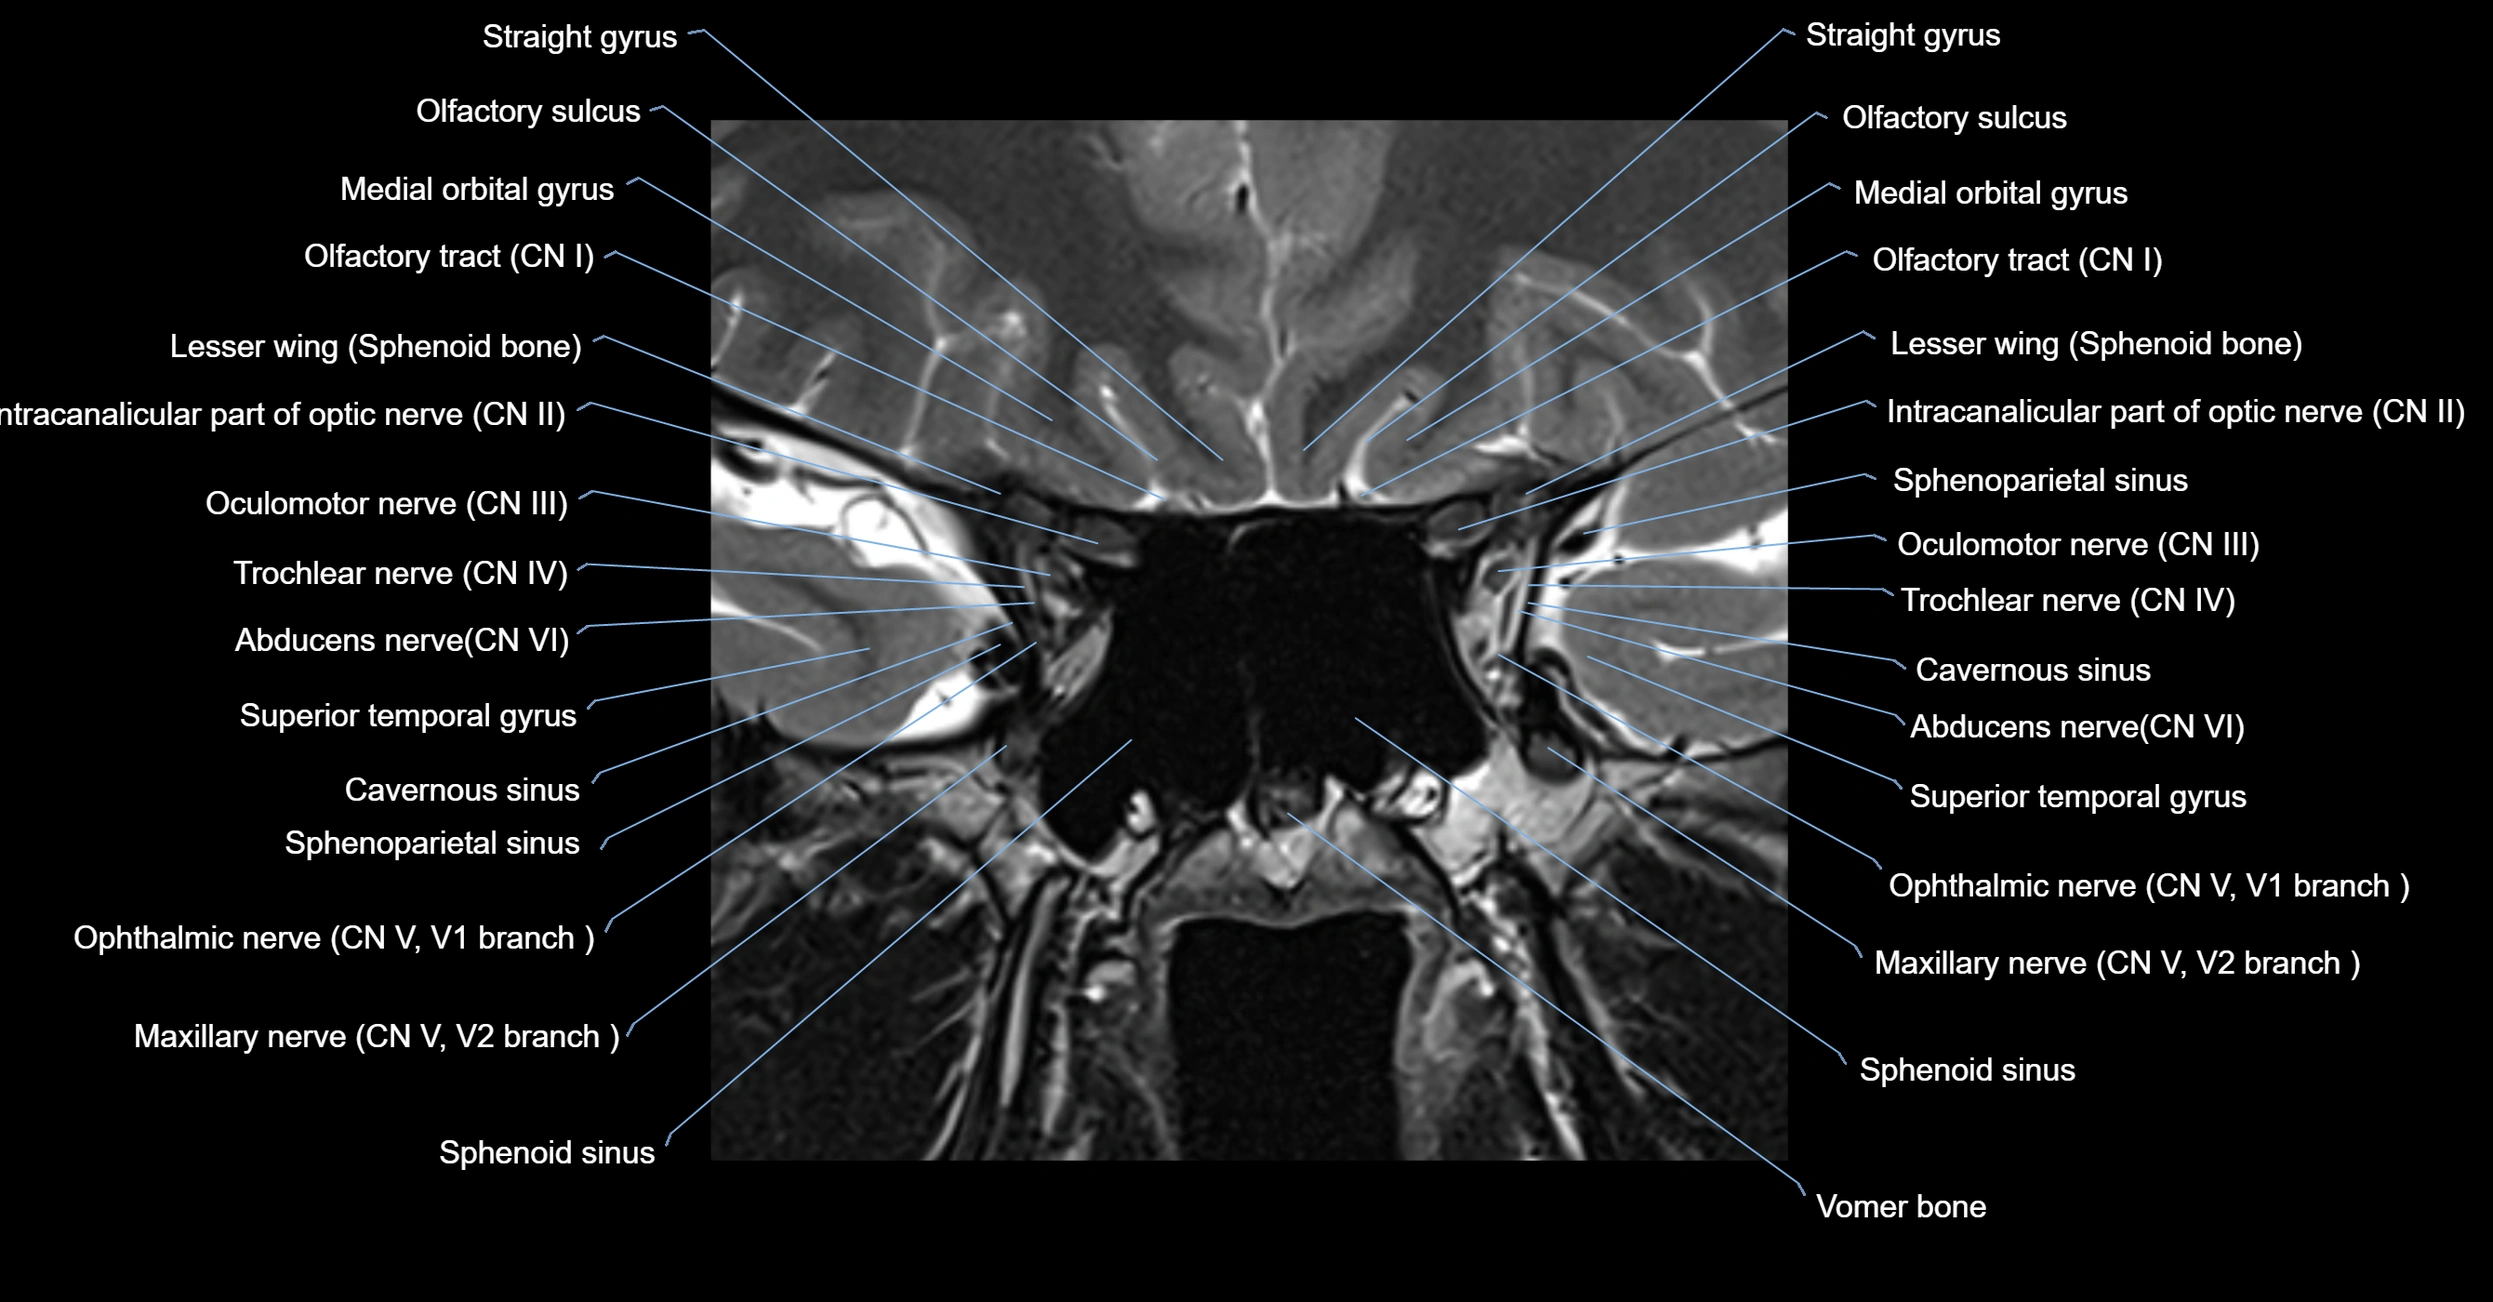

MRI Appearance

The abducens nerve is a small, thin, linear structure

Best visualized on high-resolution T2-weighted 3D MRI sequences (e.g., FIESTA or CISS)

Seen as a hypointense (dark) line running from the brainstem at the pontomedullary junction, traversing the prepontine cistern, and entering Dorello’s canal under the petrosphenoidal ligament, then into the cavernous sinus, and finally the orbit

May be challenging to visualize in standard MRI due to its small size

Pathology may be inferred by absence, displacement, or enhancement of the nerve

MRI images